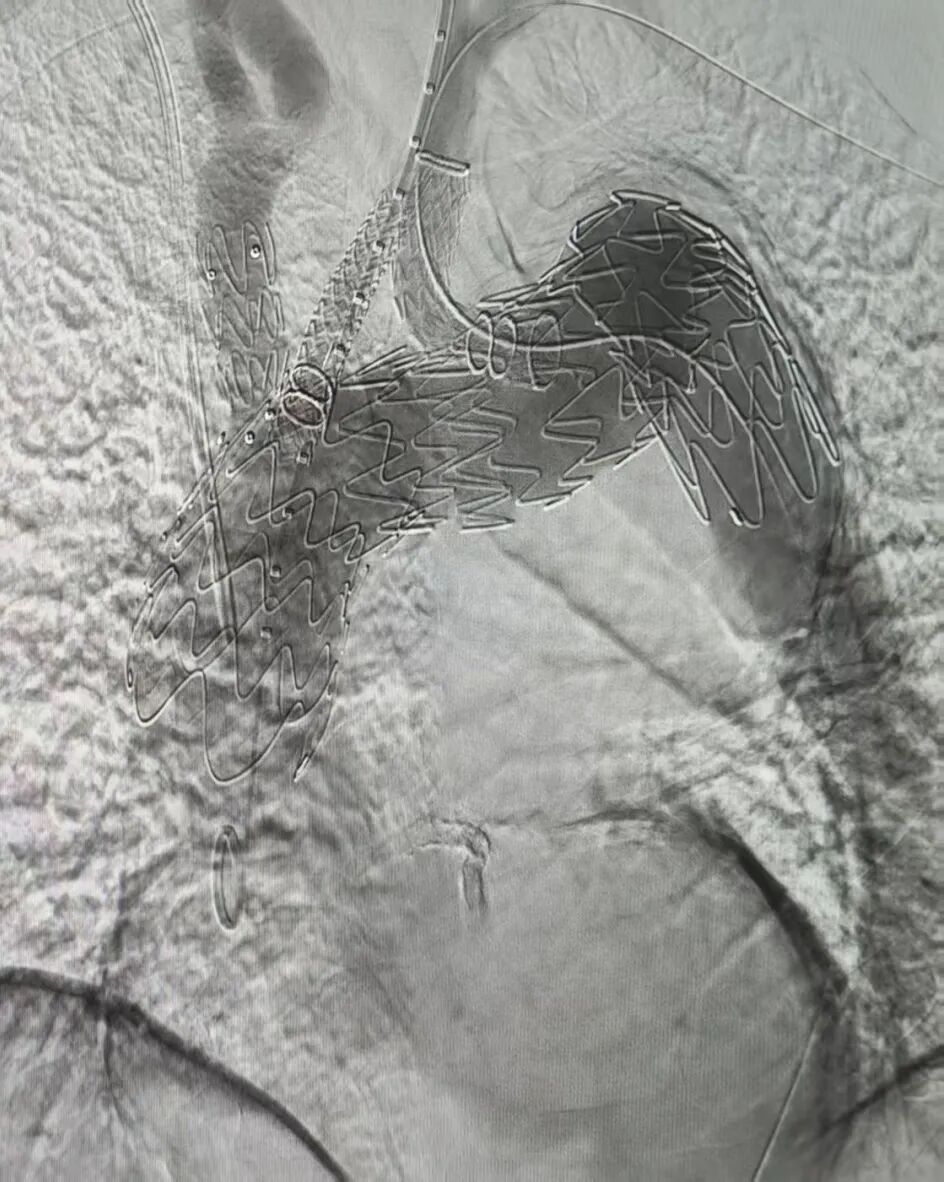

马来西亚病例分享

马来西亚病例手术在诺灯心血管医院(Northern Heart Hospital Penang)由Edward Choke教授及其团队实施。该患者诊断为累及左颈总动脉的弓上动脉瘤,瘤体直径达6.5cm,弓部小弯侧无适合常规支架的健康锚定区。为确保瘤体有效隔绝,需将覆膜支架近端锚定区前移至升主动脉,并重建弓上三分支。手术团队经综合评估,确认Hector?/通天戟?胸主多分支支架能够在单次腔内手术中实现全部治疗目标。术中,Hector?/通天戟?胸主多分支支架主体被精确定位并顺利展开,随后左颈总动脉分支在支架下沉区预留的空间内顺利完成超选,左锁骨下动脉分支在预埋导管的辅助下也成功完成导丝通道建立和桥接支架释放。整个手术过程顺利,未发生术中并发症,术后造影显示动脉瘤隔绝效果良好,分支血管血流通畅。

▲术中造影